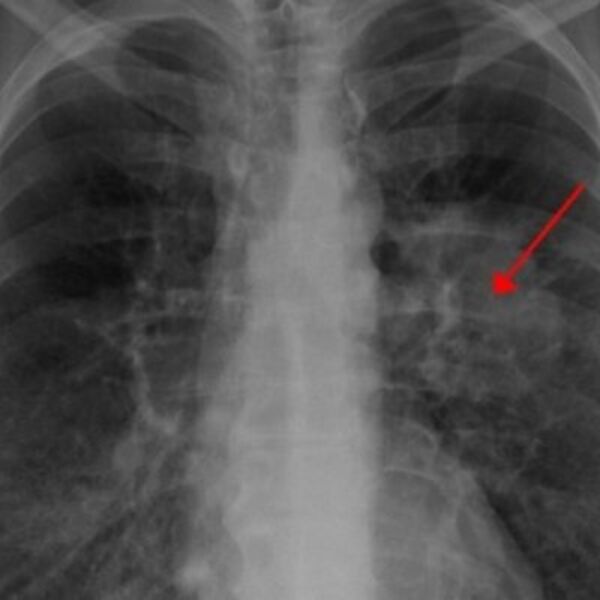

Direktor Klinike za pulmologiju objasnio sve o raku pluća u Srbiji - koliko ljudi obolevaju, koji su simptomi i koje su opcije za lečenje.

Rak pluća svakog dana odnese 13 života, a u Srbiji dnevno oboli najmanje 20 ljudi, dok smo po smrtnosti od ove maligne bolesti prvi u Evropi.

Dr Stjepanović ističe da su pluća veliki organ, te da se nekad desi da tumor poraste i nekoliko centimetara pre nego što se jave neki ozbiljni simptomi.